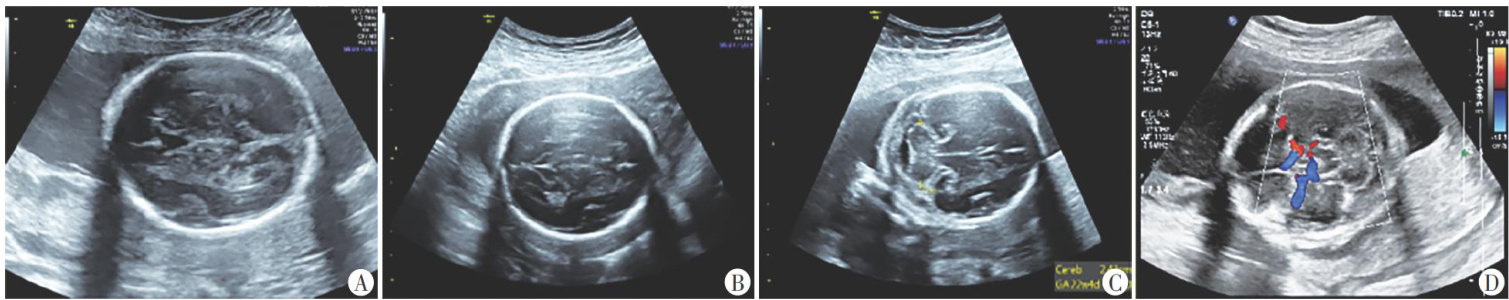

摘要目的应用经胸超声心动图(TTE)测量功能性二尖瓣反流(FMR)患者经导管二尖瓣缘对缘修复术(TEER)相关解剖参数,探讨其在评估TEER解剖适应证中的临床价值。方法选取我院经TTE初诊为FMR的患者220例,应用TTE、经食管超声心动图(TEE)分别获取患者TEER相关解剖参数,包括前瓣长度(ALL)、后瓣长度(PLL)、二尖瓣口面积(MVA)对合长度(CL)对合高度(CH)、房间隔总长(IAS),比较二者测值的差异;分别采用Pearson相关分析法和组内相关系数(ICC)分析TTE与TEE测值的相关性和一致性。以TEE分区结果为金标准,分析TTE在评估"绿区-黄区-红区"解剖适应证分类中的诊断效能。采用ICC评估TTE测量TEER相关解剖参数在观察者内及观察者间的一致性。结果TTE测量的MVA、CH、CD均高于TEE测值,差异均有统计学意义(均 P<0.05 );TTE与TEE测量的AML、PML、IAS比较差异均无统计学意义。TTE与TEE测量的ALL、PLL、MVA、CH、IAS均表现出高度相关 (r=0.864,0.833,0.955,0.896, 0.967,均 P<0.001 )及良好一致性 (ICC=0.862,0.831,0.936,0.884,0.967, 均 P<0.001 ),CL表现出中度相关 (r=0.569,P<0.001 )及较差一致性 (ICC=0.422,P<0.001) 。TTE评估FMR患者TEER三分区解剖适应证的整体准确率为 88.6% ,评估"绿区”的灵敏度、特异度、准确率分别为 98.3%.62.5%.90.5% ,评估“黄区"的灵敏度、特异度、准确率分别为 45.5% 、 96.3% 、86.6% ,评估"红区"的灵敏度、特异度、准确率分别为 73.3%.100% 98.2%。TTE测量的ALL、PLL、MVA、CL、CH、IAS在观察者内ICC分别为 0.834,0.839,0.978,0.430,0.842,0.987 (均 P<0.001 ),在观察者间ICC分别为 0.790,0.983,0.976 0.430、0.789、0.982(均 P<0.001 ),表明ALL、PLL、MVA、 CH 、IAS在观察者内及观察者间的一致性均良好,CL的一致性较差。结论TE在评估FMR患者“绿区-黄区-红区"TEER